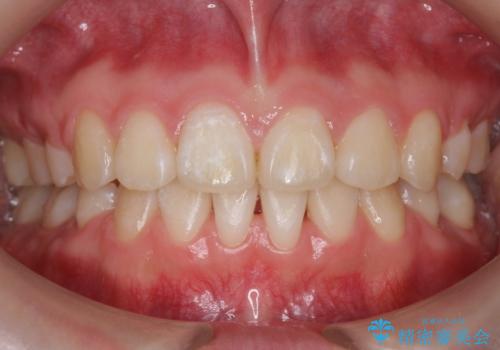

インビザラインで前歯のがたつきを目立たずに矯正治療